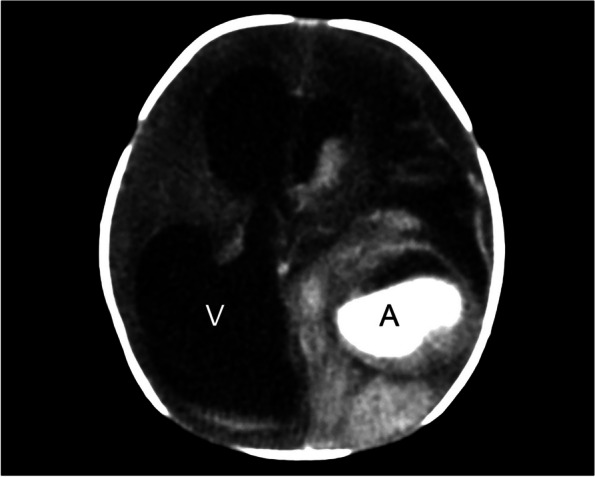

Fig. 4.

Neonatal CT brain with contrast on day 1 after birth shows marked ventriculomegaly (V) and bright hyperechoic area representing active flow in the aneurysm (A), surrounded by hyperechoic area of hemorrhage